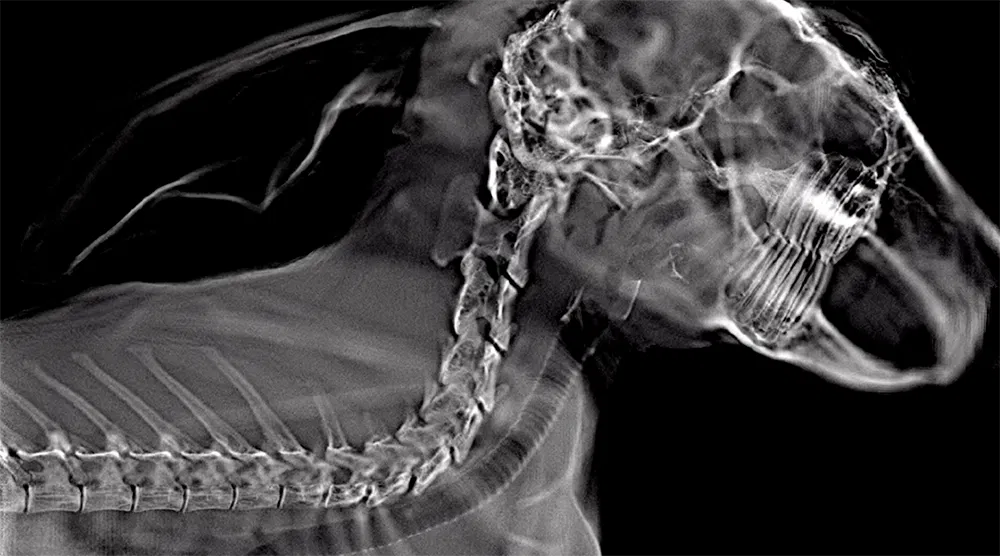

This week Adaptix will be visiting the London Vet Show to look for applications of mobile 3D X-ray imaging. In cases that require 3D imaging, this could save many customers the time and expensive of referral for an off-site CT scan, and help practices that do not have space to accommodate a CT scanner. Our tomosynthesis system provides a stack of slices through the 3D volume.

The attached images show tomosynthesis slices at two different depths through a cat’s paw and a central slice through a cat’s head.